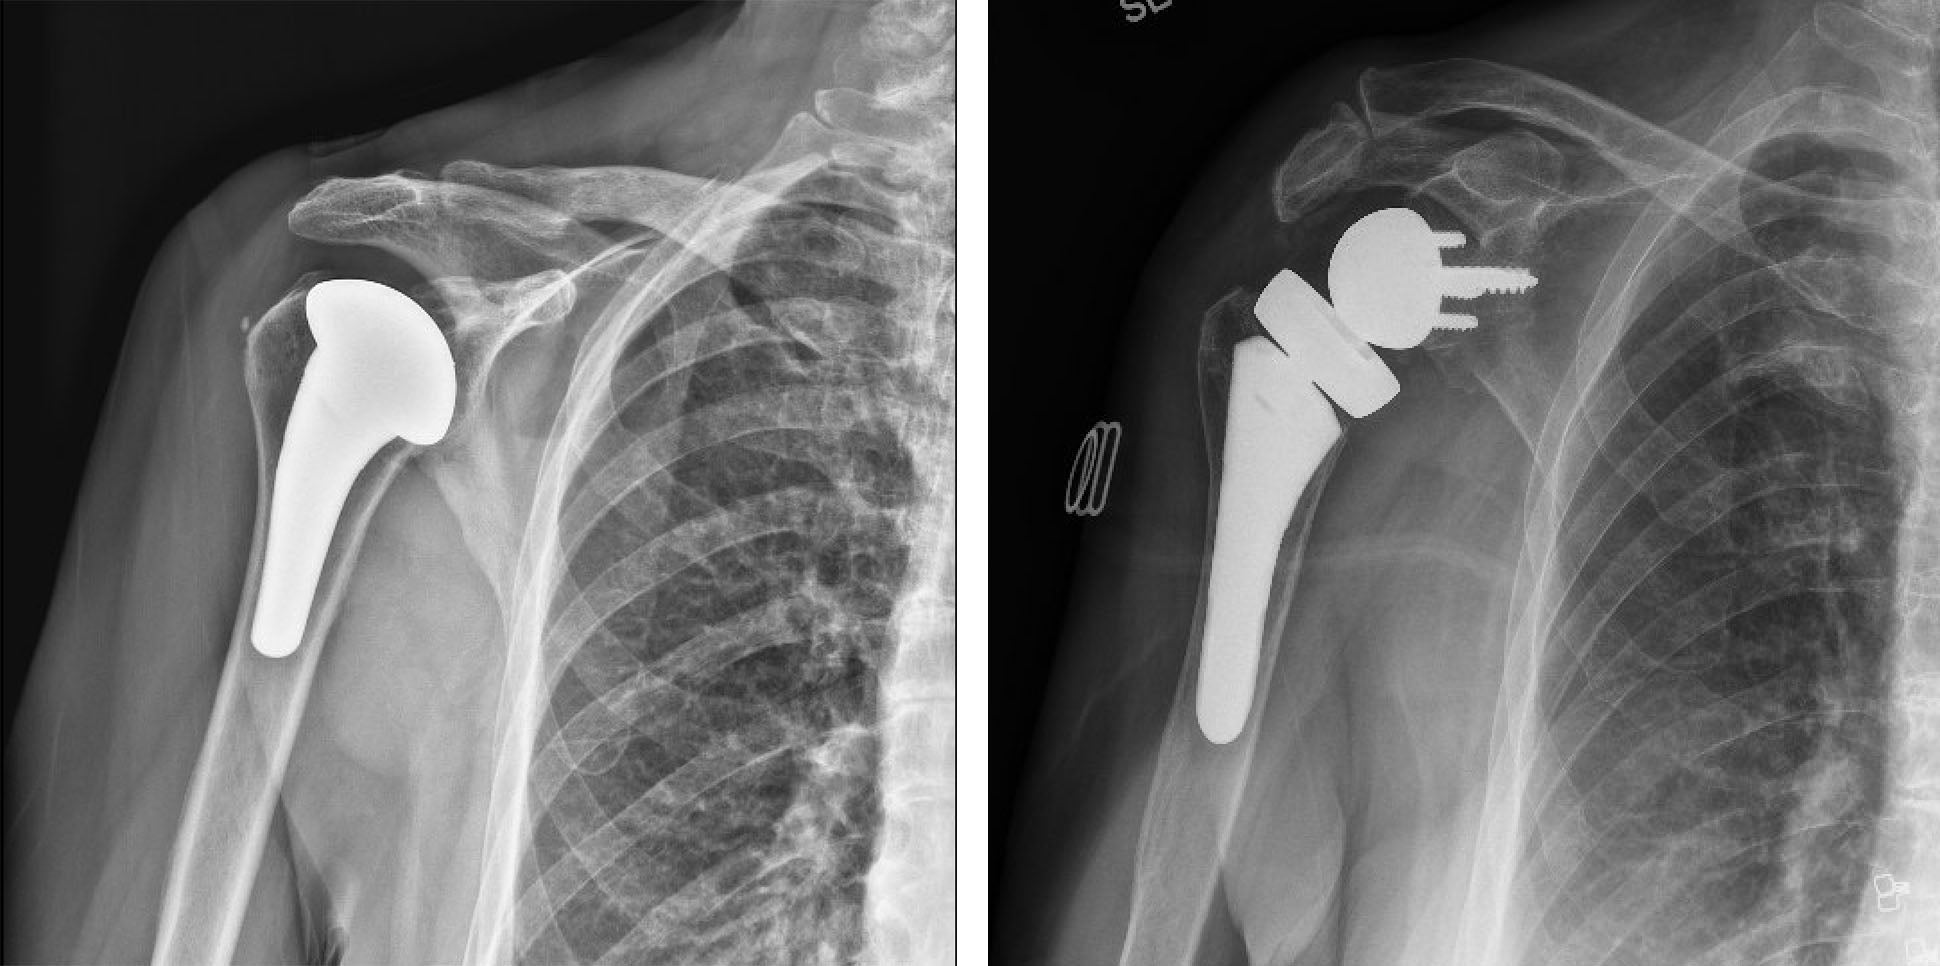

Total shoulder replacement surgery

For those with persistent pain despite non-surgical management, shoulder replacement has been shown to have excellent outcomes allowing you to return to sports and daily activities. In a traditional shoulder replacement, the worn ball of the shoulder is removed and replaced by a metal ball, while the worn shoulder socket is replaced by a strong plastic shoulder socket which is fixed in place with bone cement. This has proven to be an effective solution if you have osteoarthritis and a functioning rotator cuff, with 10-year survival rate of over 90%.

Reverse total shoulder replacement

For patients with arthritis due to a torn rotator cuff or inflammatory arthritis, a reverse shoulder replacement may be recommended. This involves “reversing” the positions of the metal ball and plastic socket. A metal ball is attached to where the socket would normally be, while a plastic socket is attached to where the ball would normally be. This changes the center of rotation of the shoulder and allows other muscles in the shoulder to compensate for an absent or non-functioning rotator cuff. While shoulder range of motion is slightly less using a reverse shoulder replacement compared to a traditional shoulder replacement, the reverse shoulder replacement is more versatile and can be used in cases where there is significant bony erosion or deformity in the shoulder joint.

Conventional vs. Reverse Total Shoulder Replacement